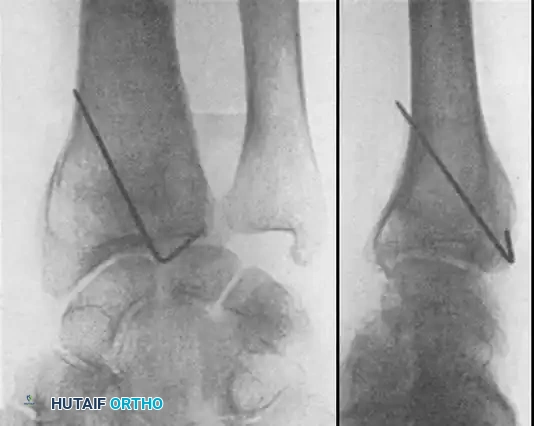

Percutaneous Pinning of Type I Fractures

If maintenance of reduction of Colles or Smith fractures requires prolonged immobilization, or if reduction is lost early, closed reduction followed by percutaneous pinning is highly effective.

TECHNIQUE 54-18

* Manipulate and reduce the fracture using longitudinal traction and appropriate counter-forces.

* Insert two large, unthreaded Kirschner wires (K-wires) through the radial styloid across the fracture and into the opposite metaphyseal cortex using a power drill, while an assistant maintains the reduction.

* Confirm good reduction and pin placement with image intensification.

* Cut the pins off beneath the skin. This provides sufficient fixation to minimize radial collapse and shortening, allowing immobilization in a cast with the wrist in a neutral position.